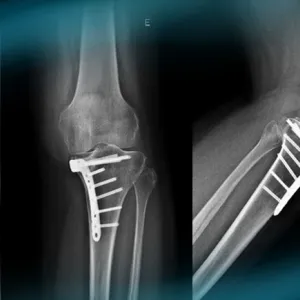

The goals of this clinical case are to discuss the different therapeutic options in case of vicious callus of the proximal tibia, to discuss the physical examination of an unstable knee, and to propose an innovative technique.